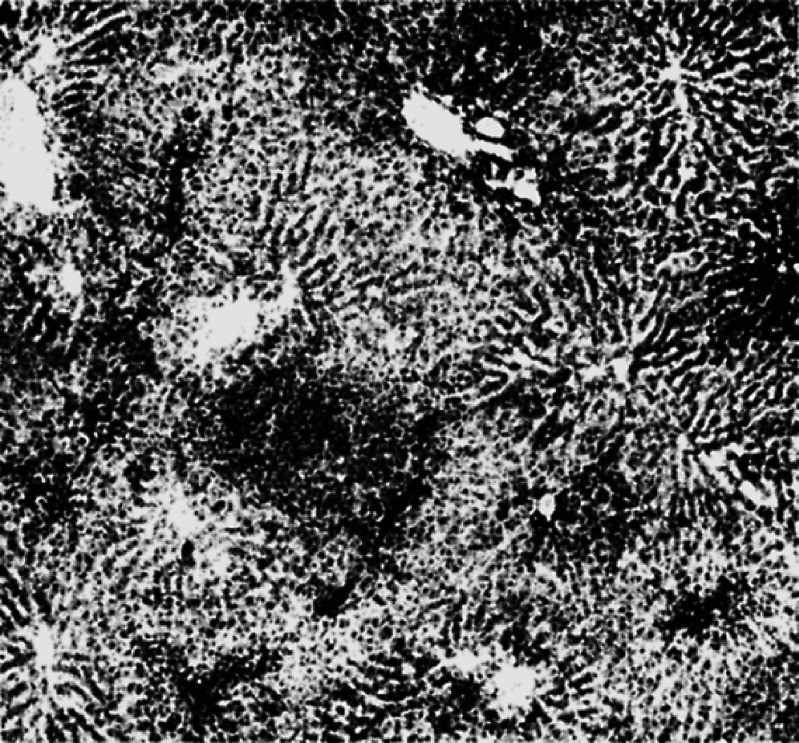

Fig. 6.

Rosette-forming hepatoma. Feeding on rice with o-aminoazotoluene for 270 days. (From Abbildung 21 of Ref. 6.)